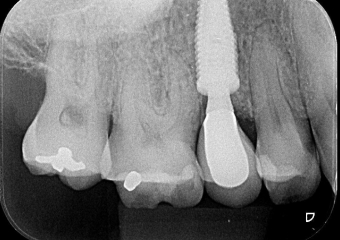

Elemento 15 fraturado

Rx Imediato